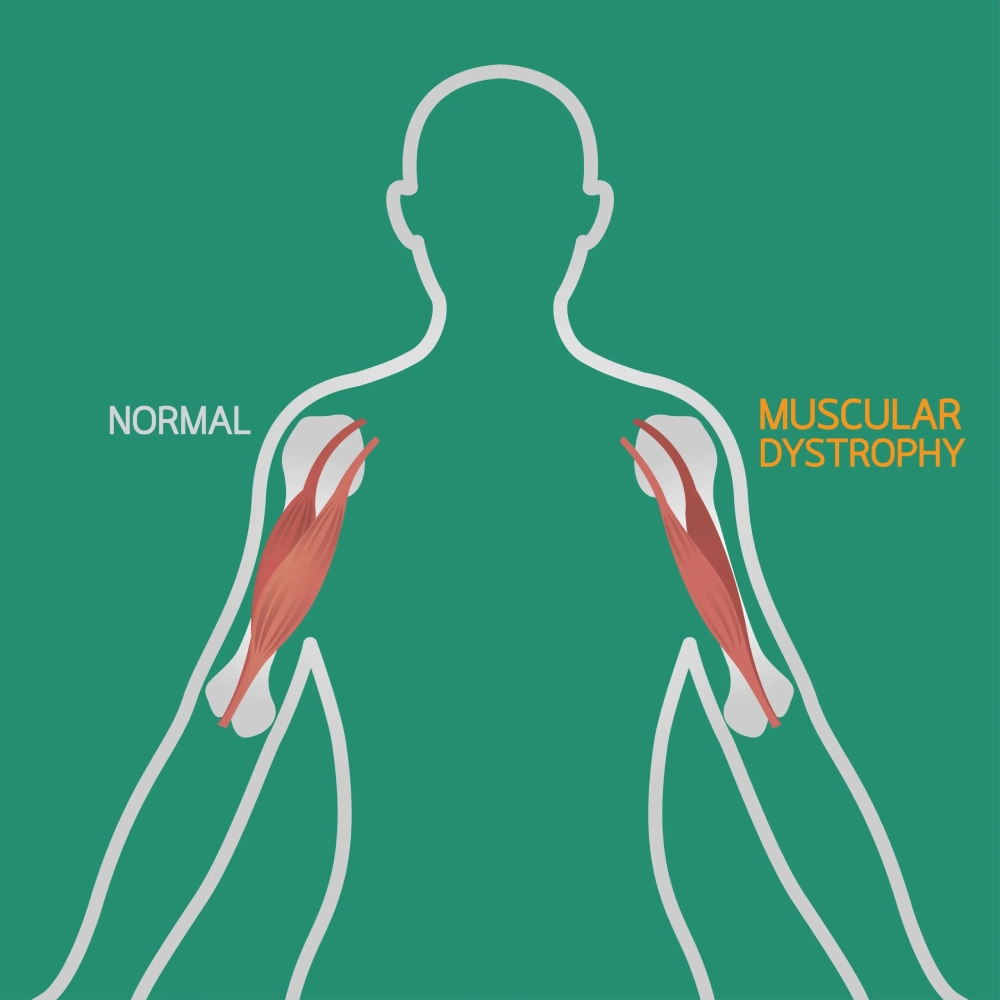

سارکولما یا غشای سلولی عضلانی در این بیماران دچار آسیبهای مکرر میشود و توانایی ترمیم خود را از دست میدهد. میوسیتها یا سلولهای عضلانی به تدریج با بافت فیبروزی و چربی جایگزین میشوند و این فرآیند دژنراتیو باعث کاهش تدریجی قدرت عضلانی میگردد. کینازهای سرمی عضلانی، به ویژه کراتین فسفوکیناز (CPK) در آزمایشهای خون این بیماران به شدت افزایش مییابد که نشاندهنده تخریب فعال بافت عضلانی است.

فرآیند آسیبشناسی دیستروفی عضلانی شامل یک چرخه مخرب است که در آن سلولهای عضلانی آسیب میبینند، تلاش برای ترمیم میکنند، اما به دلیل نقص پروتئینی نمیتوانند به طور کامل بازسازی شوند. با هر چرخه آسیب و ترمیم، تعداد بیشتری از سلولهای عضلانی از بین میروند و با بافت فیبروزی و چربی جایگزین میشوند. این فرآیند منجر به کاهش تدریجی قدرت عضلانی و افزایش ناتوانی میشود.